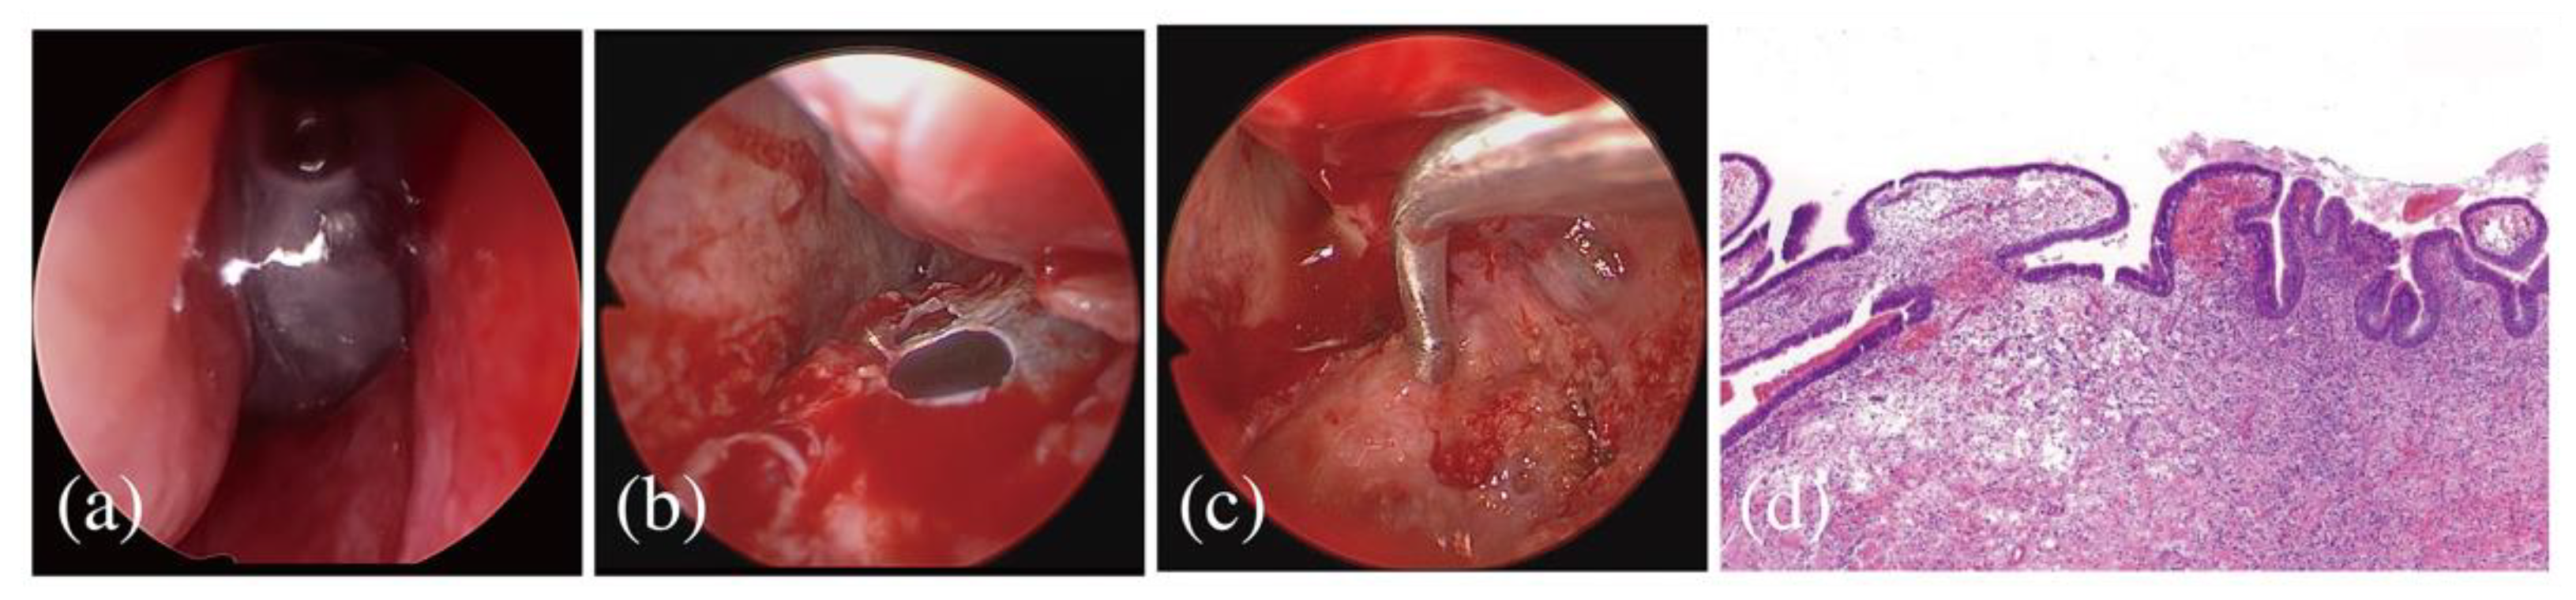

2.3. Referral to an Otolaryngological Specialist